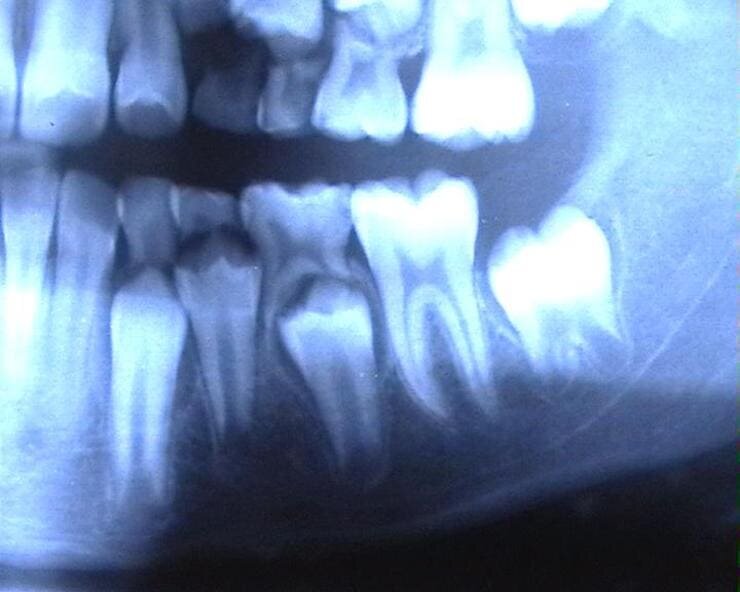

Рентген-снимок зубов: видны закладки постоянных зубов под прорезавшимися молочными